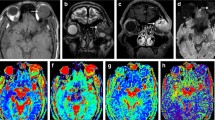

All the post-processing steps were performed using the Olea Sphere® software (v3.0, Olea Medical, La Ciotat, France), implementing a Bayesian probability-based algorithm using all 15 b-values to fit a biexponential diffusion model to each voxel within a region of interest (ROI) for the calculation of IVIM parameters (D, D* and f), and a monoexponential diffusion model for the calculation of ADC (Fig. 1).

A 47-year-old man with a cavernous haemangioma in his left orbit (asterisk), displacing the eye anteriorly, as shown on the axial post-contrast T1 WI (a). Placement of a freehand large region of interest (ROI) (yellow line) and of a circular small ROI (red circle) inside the mass are shown (b). Test (c) and retest (d) bi-exponential fitting curves using b values are shown. Coloured intravoxel incoherent motion (IVIM) parametric map is displayed (e)

The operators independently drew seven ROIs on each imaging set: two ROIs inside the orbital mass, the first one encompassing the maximum area of the orbital mass (ROI 1) and the second one a circular ROI at the centre of the orbital mass without consideration for the zones with restricted diffusion or with enhancing nodules if present (ROI 2) (Fig. 1), three ROIs in non-tumoral orbital structures: in the contralateral lacrymal gland (ROI 3), in the contralateral medial (ROI 4) and lateral (ROI 5) extra-ocular muscles, and two ROIs outside the orbit: one ROI in the temporal muscle (ROI 6) and one ROI in the contralateral temporal lobe white matter (ROI 7). The five last ROIs were drawn in order to analyse their repeatability, in case they might be used in further studies as structures of reference to normalise IVIM values (as is done sometimes in brain studies [10, 21]). Size and location of the ROIs in the orbital and encephalic locations was kept constant across patients to every possible extent, except for ROI 1, which encompassed the largest possible portion of the mass on the slice including its largest diameter. ROIs were placed on the transverse b0 image and propagated to all b-values, ADC and IVIM parametric maps. Readers were free to review the other structural images to ease the drawing of the ROI. A direct registration between the structural and the IVIM images was not possible due to the distortions seen on the IVIM images.